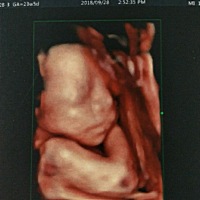

希望宝宝健康平安